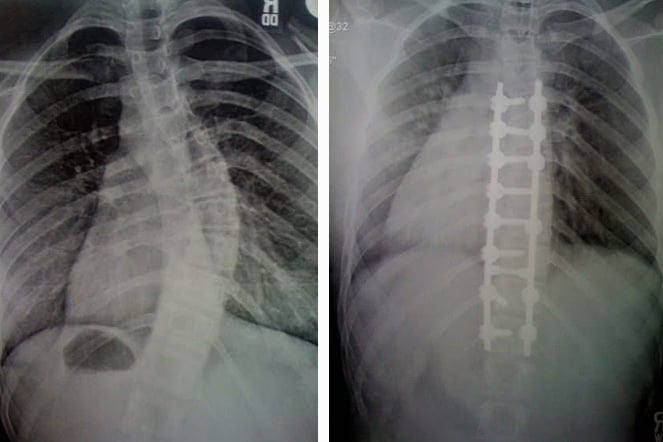

a before and after x-ray of a spine after spinal fusion surgery

Ollie's X-ray images show incredible results from their spinal fusion.